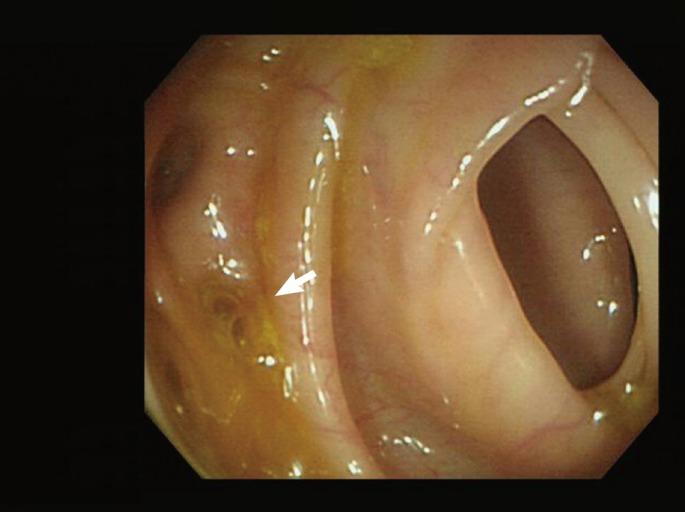

Colouterine fistula is an extremely rare condition because the uterus is a thick, muscular organ. Here, we present a case of a colouterine fistula secondary to colonic diverticulitis. An 81-year-old woman was referred to the emergency department with abdominal pain and vaginal discharge. Computed tomography showed a myometrial abscess cavity in the uterus adherent to the thick sigmoid wall. Upon contrast injection via the cervical os for fistulography, we observed spillage of the contrast into the sigmoid colon via the uterine fundus. Inflammatory adhesion of the distal sigmoid colon to the posterior wall of the uterus was found during surgery. The colon was dissected off the uterus. Resection of the sigmoid colon, primary anastomosis, and repair of the fistula tract of the uterus were performed. The postoperative course was uneventful. This case represents an unusual type of diverticulitis complication and illustrates diagnostic procedures and surgical management for a colouterine fistula.

子宫结肠瘘极为罕见,因为子宫是一个厚实的肌肉器官。在此,我们报告一例继发于结肠憩室炎的子宫结肠瘘病例。一名81岁女性因腹痛和阴道分泌物增多被转诊至急诊科。计算机断层扫描显示子宫肌层有一个脓肿腔,与增厚的乙状结肠壁粘连。通过宫颈口注入造影剂进行瘘管造影时,我们观察到造影剂经子宫底部溢入乙状结肠。手术中发现乙状结肠远端与子宫后壁存在炎性粘连。将结肠从子宫上分离。进行了乙状结肠切除、一期吻合以及子宫瘘管修复。术后过程顺利。该病例代表了一种不寻常类型的憩室炎并发症,并说明了子宫结肠瘘的诊断方法和手术治疗。